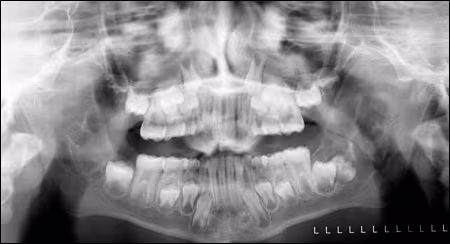

The current radiograph (Figure 6), three years from first discovery, showed continued enlargement with an almost bilaterally symmetrical appearance to the lesions.

Figure 6. Panoramic radiograph demonstrating bilateral multilocular lesions involving the body, angle, and ramus areas of the mandible at the most recent evaluation of the patient in December 2007.